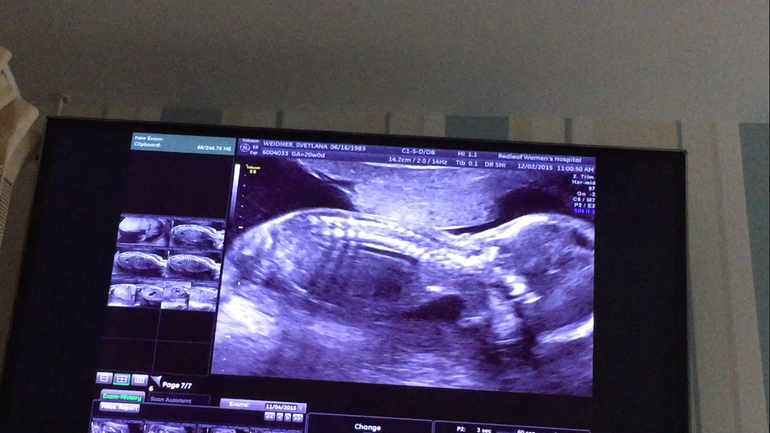

Ну и что ещё на последок. Ах да! Сделали фотосессию, конечно! Фото изумительные, будут готовы через 2 недели. Вот, что мне украдкой удалось сфотографировать с экрана компьютера, когда отбирала лучшие снимки: